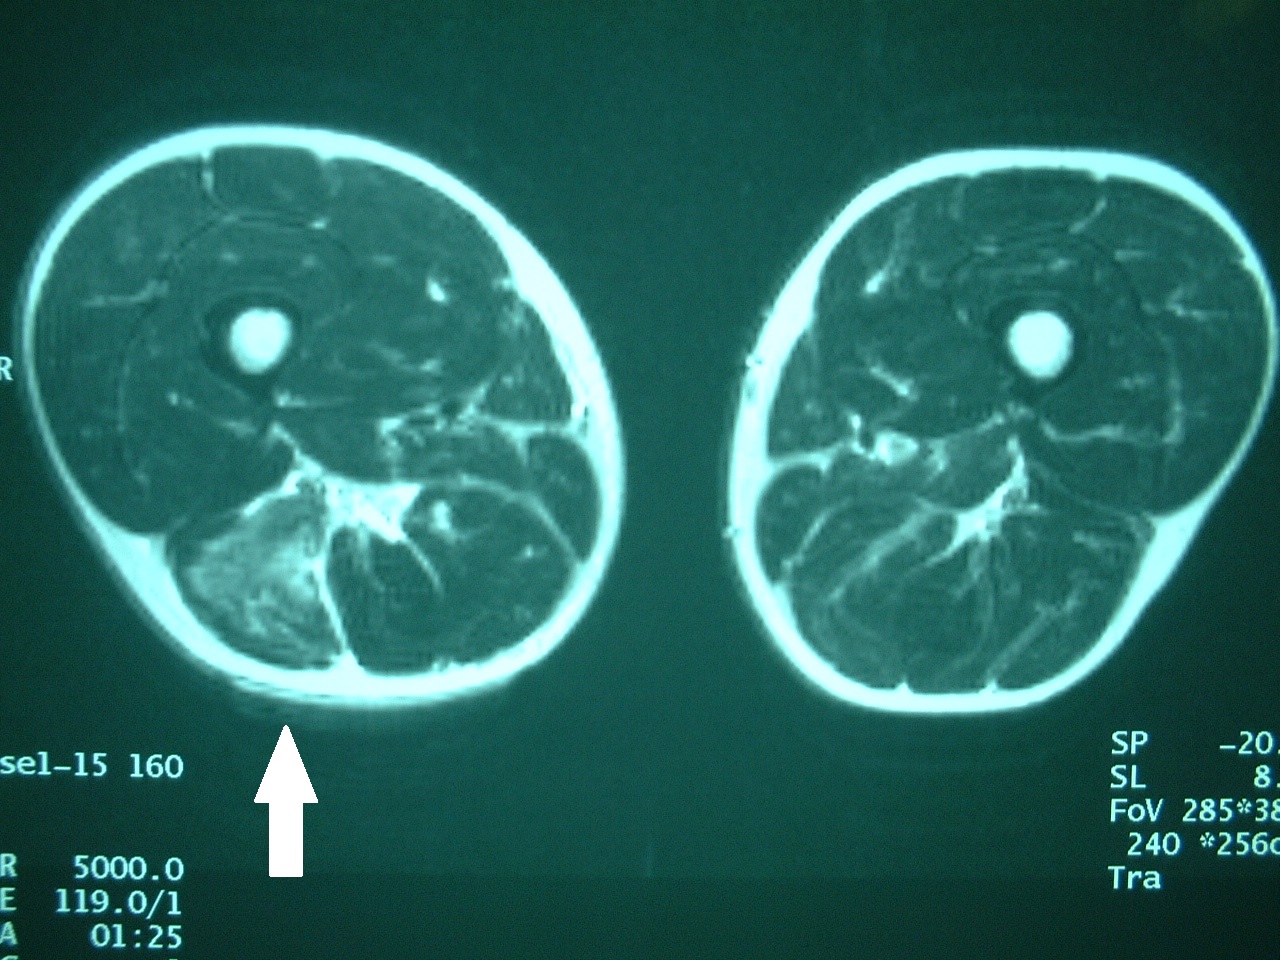

![]() 肉離れに対するリハビリテーション 古東整形外科 リウマチ科  | ![]() 肉離れに対するリハビリテーション 古東整形外科 リウマチ科  | 肉離れに対するリハビリテーション 古東整形外科 リウマチ科  |

肉離れに対するリハビリテーション 古東整形外科 リウマチ科  | ![]() 肉離れに対するリハビリテーション 古東整形外科 リウマチ科  | ![]() 肉離れに対するリハビリテーション 古東整形外科 リウマチ科  |

![]() 肉離れに対するリハビリテーション 古東整形外科 リウマチ科  | ![]() 肉離れに対するリハビリテーション 古東整形外科 リウマチ科  | ![]() 肉離れに対するリハビリテーション 古東整形外科 リウマチ科  |

「肉離れ 軽度 1週間」の画像ギャラリー、詳細は各画像をクリックしてください。